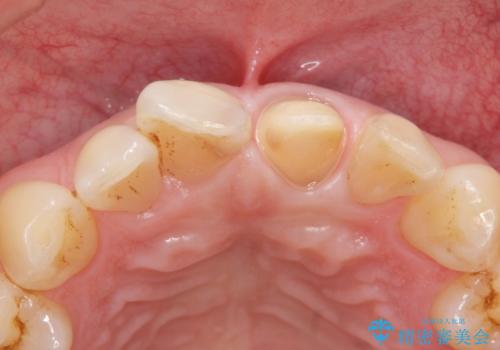

レジンを除去したところ二次う蝕を認めたため、丁寧に虫歯をとりました。

歯の欠損範囲が大きいことから、同様にレジン修復しても欠けやすいためセラミッククラウンによる補綴を行いました。

患者様のご希望により、最終補綴前にホワイトニングを行いました。